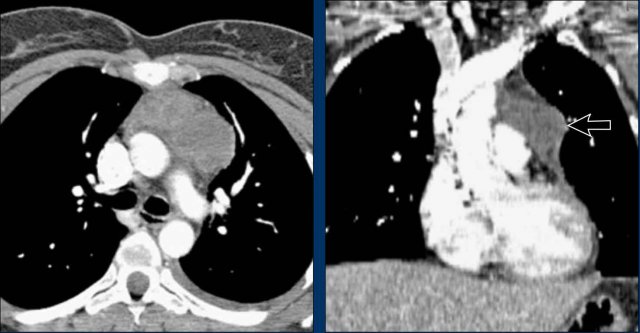

Postoperative Pericardial Hemorrhage

In patients with recent cardiac surgery, a sudden change in heart size on chest X-ray should raise suspicion for pericardial bleeding, which may be life-threatening.

Case Example 2:

• A postoperative patient showed a change in the cardiac silhouette.

• Echocardiography detected only a minimal pericardial effusion.

Case Example 2 - CT imaging

• CT imaging revealed a large posterior pericardial effusion compressing the left ventricle (blue arrow: effusion; red arrow: compressed, contrast-filled left ventricle).

• Surgical exploration confirmed a large posterior pericardial hematoma.

Note

: Minimal anterior fluid on ultrasound may underestimate the true volume if the effusion is loculated posteriorly, highlighting the value of CT in postoperative cases.